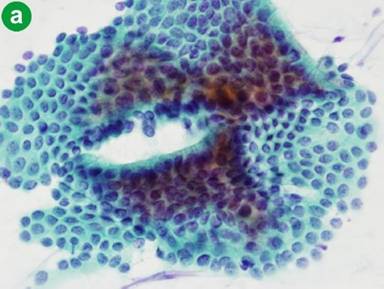

The presence of atypical cells (class III-IV-V) in pancreatic juice samples was found in 5 of 12 patients with pancreatic ductal adenocarcinoma (41.7%, 3 of class III, 2 of class IV, and none of class V) (Figure 4). The rtelationship between the pancreatic juice cytology and the expression levels of miRs in 12 patients having pancreatic ductal adenocarcinoma are shown in Figure 5. Expression levels of miR-21 in pancreatic juice of patients with a cytological result of non-atypical cells (no. 7, 58.3%; all of class II) were not significantly different from those of the atypical results (P=0.246). The same finding was observed in the expression levels of miR-155 in pancreatic juice between non-atypical and atypical results (P=0.592). Table 1 shows the details of the samples.

Figure 4. a. Non-atypical cells in pancreatic juice (x400). b. Atypical cells in pancreatic juice (x400). |